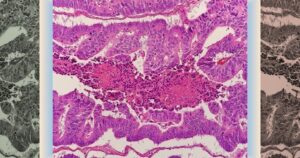

Ингибиторы ангиогенеза не повысили риск аневризм и расслоения артерий. Медики проанализировали данные пациентов с метастатическим колоректальными опухолями

Пациенты, получающие препараты ингибиторов ангиогенеза по поводу колоректальных опухолей, не подвержены повышенному риску аневризм и расслоения артерий. К такому выводу пришли французские ученые, которые провели исследование типа «случай — контроль» на выборке из более двух тысяч пациентов. Результаты работы опубликованы в JAMA Network Open. Одним из важнейших процессов в развитии новообразований (в том числе злокачественных) …